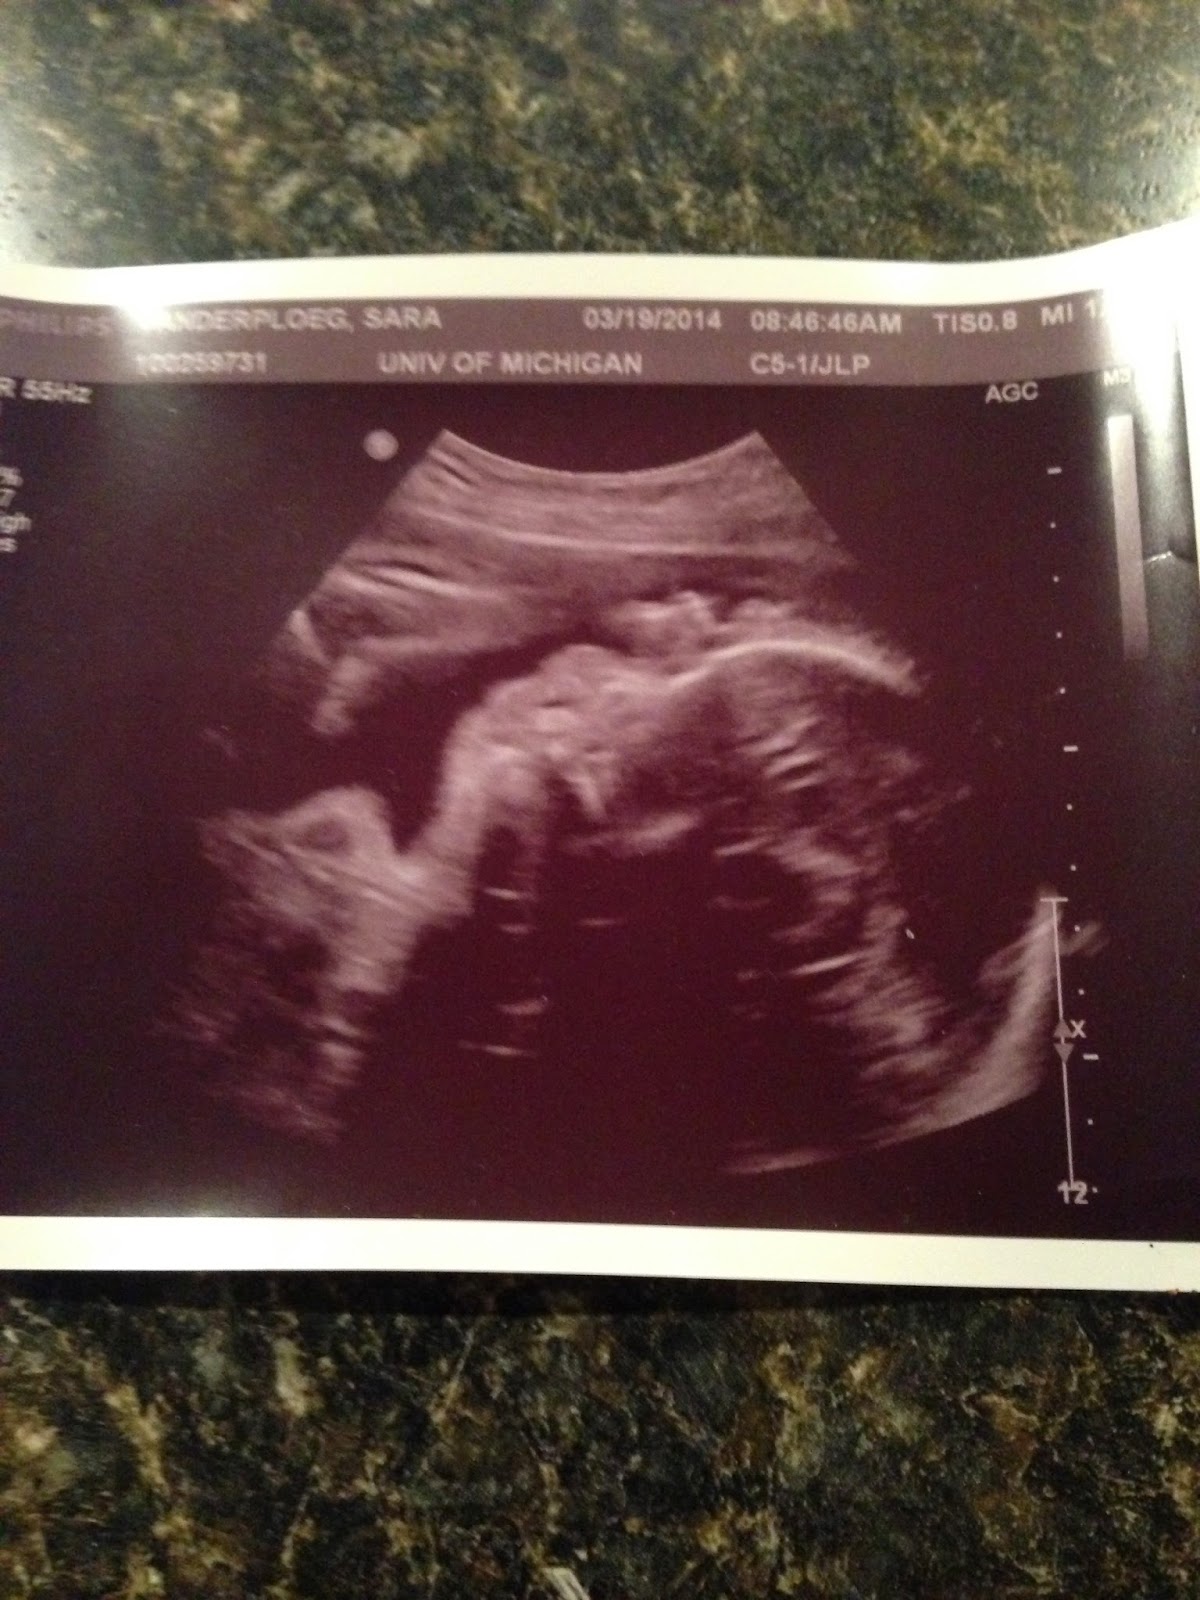

| A profile picture of Baby A |